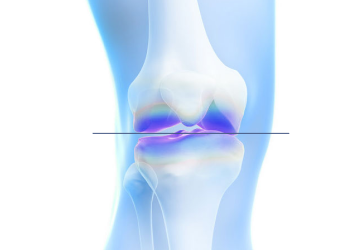

무릎 안쪽에 체중이 과도하게 실리면서 통증과 관절 손상이 진행

O자 다리

다리가 바깥쪽으로 휘어 무릎 안쪽(내측)에 체중 집중

무릎 안쪽 관절염

연골 마모 → 뼈끼리 닿으며 통증 발생